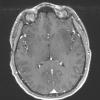

Astrocytoma, IDH-mutant, WHO Grade 2 (8)